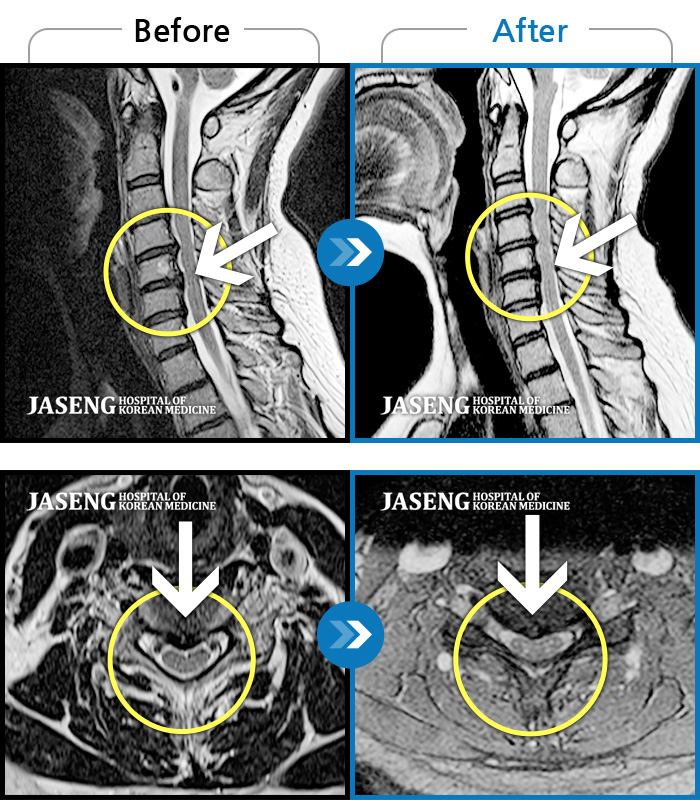

목디스크

인천 · 조남훈 원장

증상이 재발하였습니다.

촬영시기

2021.11.20 ~ 2025.11.13

2025.11.21